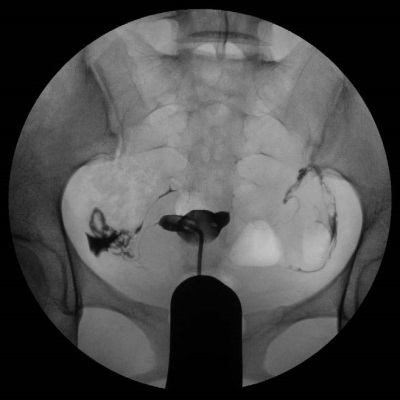

输卵管造影检查是通过导管向子宫腔及输卵管注入造影剂,利用X线诊断仪透视及摄片,根据造影剂在输卵管及盆腔内的显影情况来了解输卵管是否通畅、通畅程度、阻塞部位及宫腔形态的一种检查方法。该检查损伤小,配以高精度数字化X线成像系统使造影图像更清晰,对输卵管阻塞诊断准确率达98%,同时还具有一定的治疗作用,在许多方面是超声、CT、核磁、宫腔镜、腹腔镜、输卵管镜等检查所无法替代的。